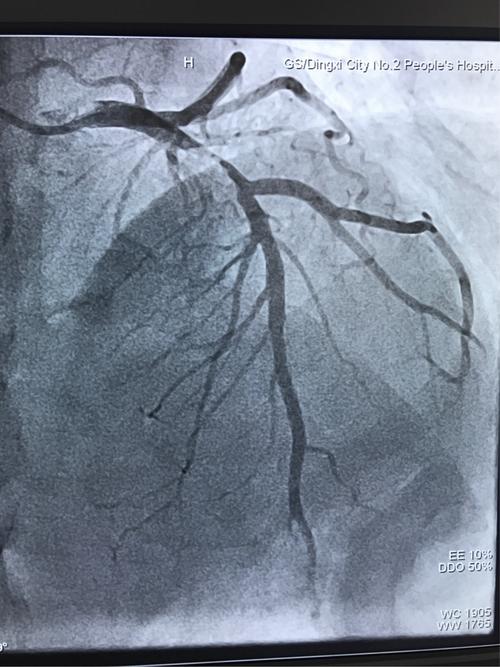

术前左前降支近段重度狭窄

头位:前降支近段重度狭窄,血流变慢